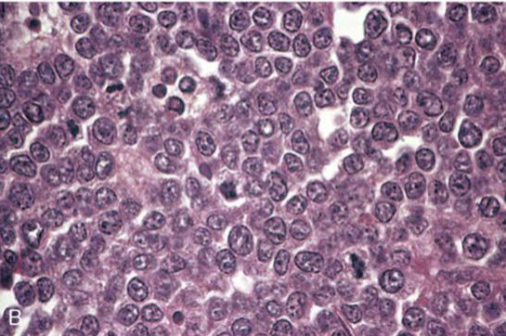

Burkitt lymphoma

Highly aggressive B-cell neoplasm characterized by the overexpression of the Myc gene on Chromosome 8

Translocation is the IgH heavy chain locus t(8;14)

Starry Sky appearance due to evenly interspersed macrophages with apoptotic debris in cytoplasm

Intermediate to small cells with noncleaved nuclei, coarse chromatin, small multiple nucleoli & very high mitotic index